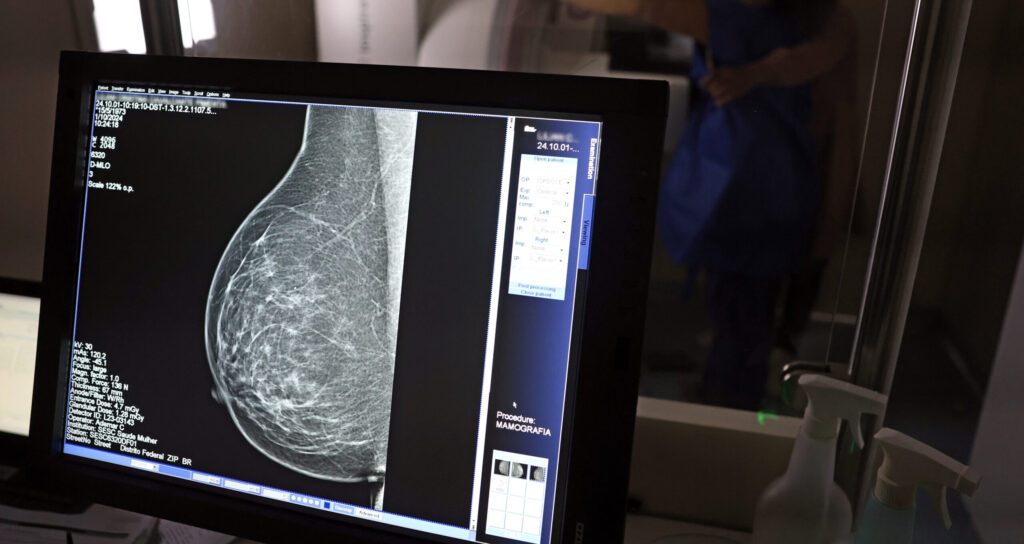

Com mais de 57 mil mamografias realizadas em 2025, o Piauí ampliou significativamente o acesso ao diagnóstico precoce do câncer de mama, especialmente entre mulheres a partir dos 40 anos. Como parte das ações de reforço ao tratamento, o estado recebeu, na quinta-feira (23), uma remessa com 224 unidades do medicamento Trastuzumabe Entansina, recém-incorporado ao Sistema Único de Saúde (SUS) para casos avançados da doença.

A rede estadual conta com 43 mamógrafos fixos e o serviço itinerante dos Caminhões da Mamografia, que percorrem os municípios levando o exame a quem mais precisa. O foco principal tem sido nas mulheres entre 40 e 49 anos, faixa etária que passou a ser atendida sob demanda, conforme nova orientação do Ministério da Saúde.

A técnica em radiologia Ana Vitória atua na Central de Diagnóstico de Valença e confirma o impacto direto na vida da população. “Antes o exame só era disponibilizado em clínica particular. Agora, mulheres de toda a região vêm aqui, fazem o agendamento e realizam o exame. Atendemos mulheres a partir dos 40 anos, sem fila, com estrutura pública. Isso melhorou muito a vida das pessoas”, afirma.